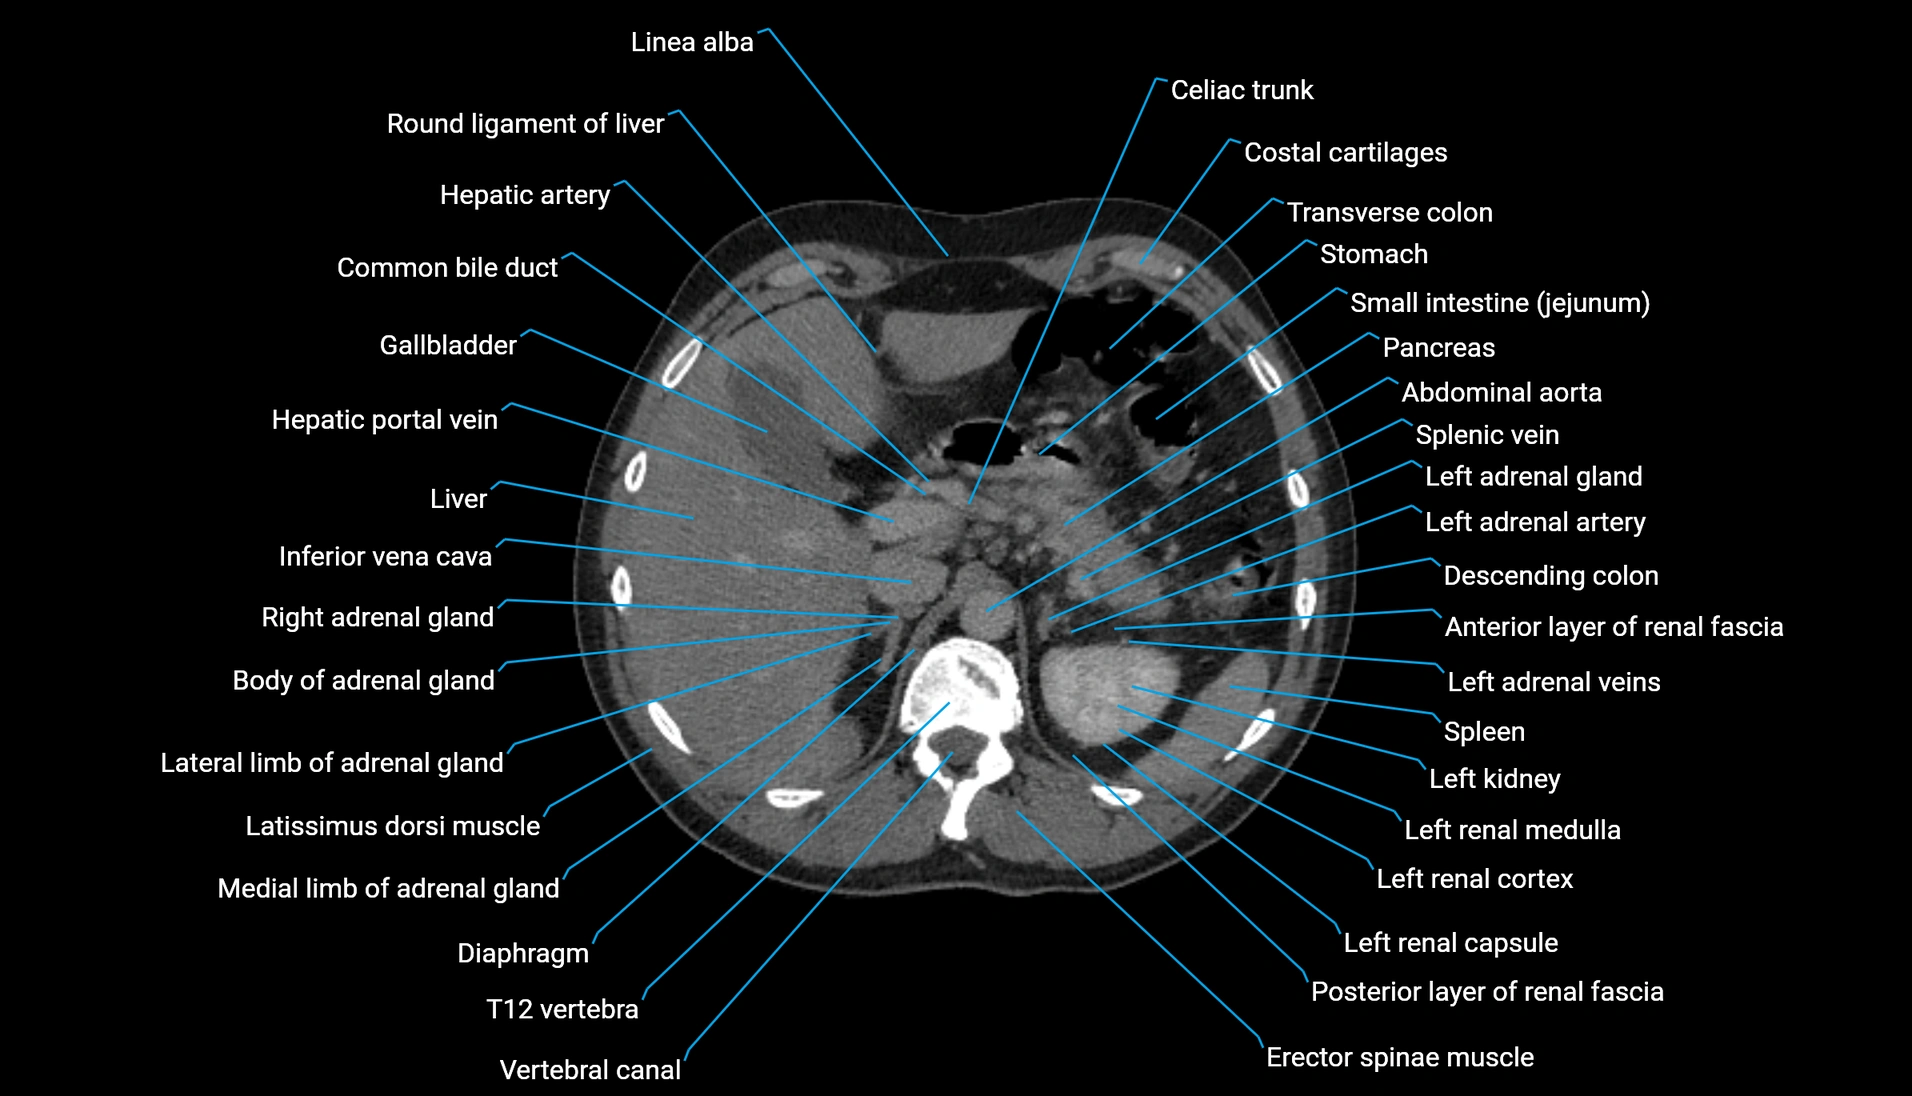

CT Appearance

Non-contrast CT:

-

Demonstrates cortical bone of acetabular rim in excellent detail

Detects fractures, dysplasia, retroversion, or bony overcoverage (pincer impingement)

3D reconstructions used in preoperative hip surgery planning

CT image